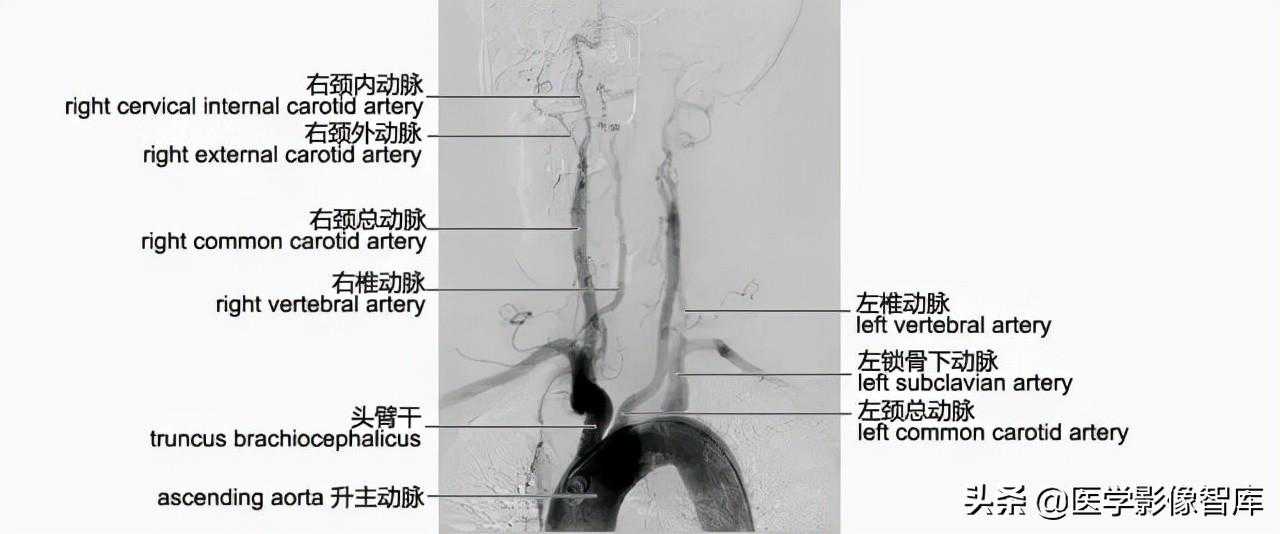

颈部血供主要来自于颈动脉和锁骨下动脉的椎动脉、甲状颈干及肋颈干。颈部静脉回流通过颈浅静脉和颈深静脉。

颈动脉造影解剖

左右两侧颈总动脉的起始部位不同,右颈总动脉起自头臂干(无名动脉),左颈总动脉起始于主动脉弓顶端,通常左颈总动脉较右颈总动脉为长。两侧颈总动脉起始位置最常见的变异有两型:一是左颈总动脉开口于无名动脉,二是左颈总动脉开口于左锁骨下动脉。颈总动脉沿食管和咽两侧上行,通常于C4椎体水平分为颈内动脉和颈外动脉,前者向后外方行走,后者向前内上行走,颈总动脉分叉高度的变异通常是双侧性的。通常在分叉之前颈总动脉主干没有分支,血管造影可见血管壁光整,管腔粗细均匀,年轻人颈总动脉较直,老年人较弯曲。颈外动脉主干发出的供应颈部的最主要分支为甲状腺上动脉,其余分支均供应头面部(图4-4-1)。

图4-4-1主动脉弓造影